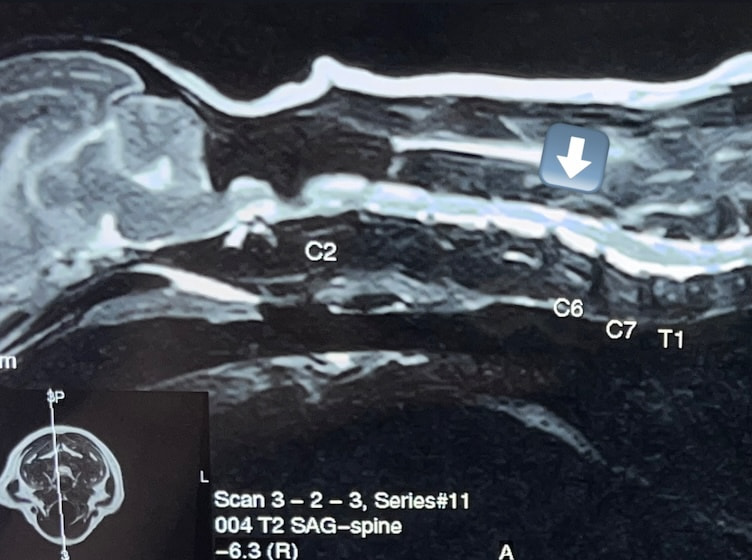

椎間板ヘルニア(2025/05/13)

椎間板ヘルニアは、背骨の椎体と椎体の間にあるクッションの様な役割を果たす椎間板が変性・突出して脊髄を圧迫し、痛み、歩行困難、麻痺などの神経症状を引き起こす疾患です。ダックスやコーギーなどの胴長短足の犬種に多く見られ、加齢やジャンプなどの衝撃が原因となることもあります。症状の程度により、内科治療や手術が行われます。当院では手術や内科治療以外にもマイクロウェーブやレーザーを用い痛みがある部分を温め、痛みを和らげる治療も行っています。歩行・姿勢に違和感を感じた際は早めにご相談下さい。